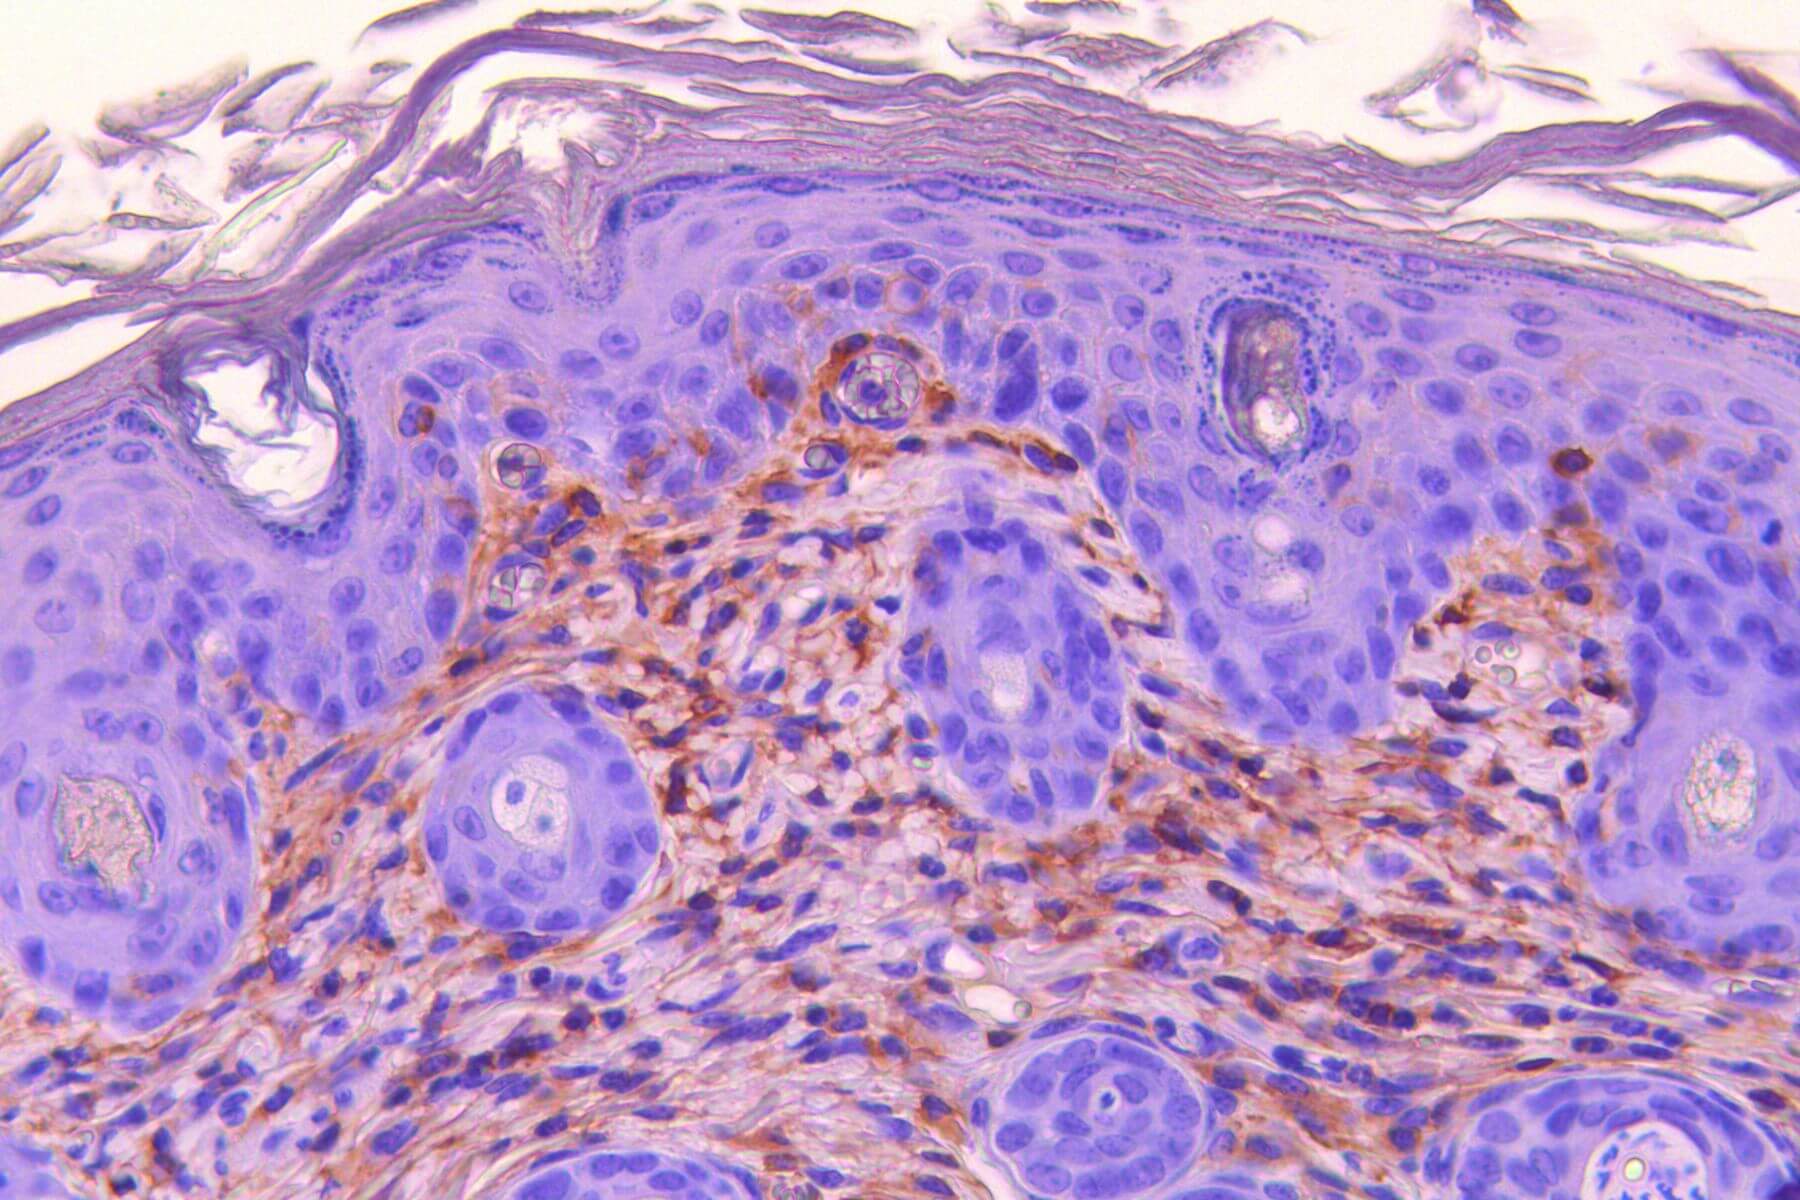

Psoriasis – Imiquimod Model

Repeated topical applications of Imiquimod in mice progressively induce inflammation (erythema), edema, and plaque‑forming scaling, mimicking psoriasis. This model integrates in situ measurements (TEWL, dermoscopy, scoring…), behavioral assessments, serum biomarker analyses (IL-17, IL-23, IL-6…), and histological/immunohistochemical evaluations. It offers high predictive value for clinical success and constitutes a robust tool to evaluate therapeutic efficacy.